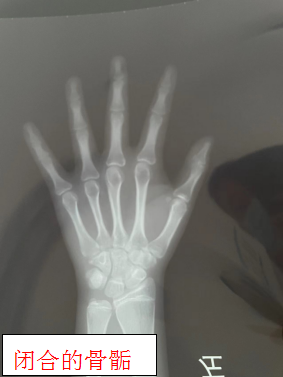

三岁之前,儿童的生长主要由营养进行调控,三岁之后,儿童的生长主要影响因素就不在是营养了而是生长激素和甲状腺素,进入青春期生长主要由性激素和生长激素进行调控。性激素在促进身高增长的同时也加速了骨骺的闭合,因此女孩出现初潮和男孩变声1-2年之后,骨骺基本闭合,身高不再增长。定期随访及骨龄监测(每半年一次)是非常重要的,防止骨骺过快闭合而错失生长发育关键时期。